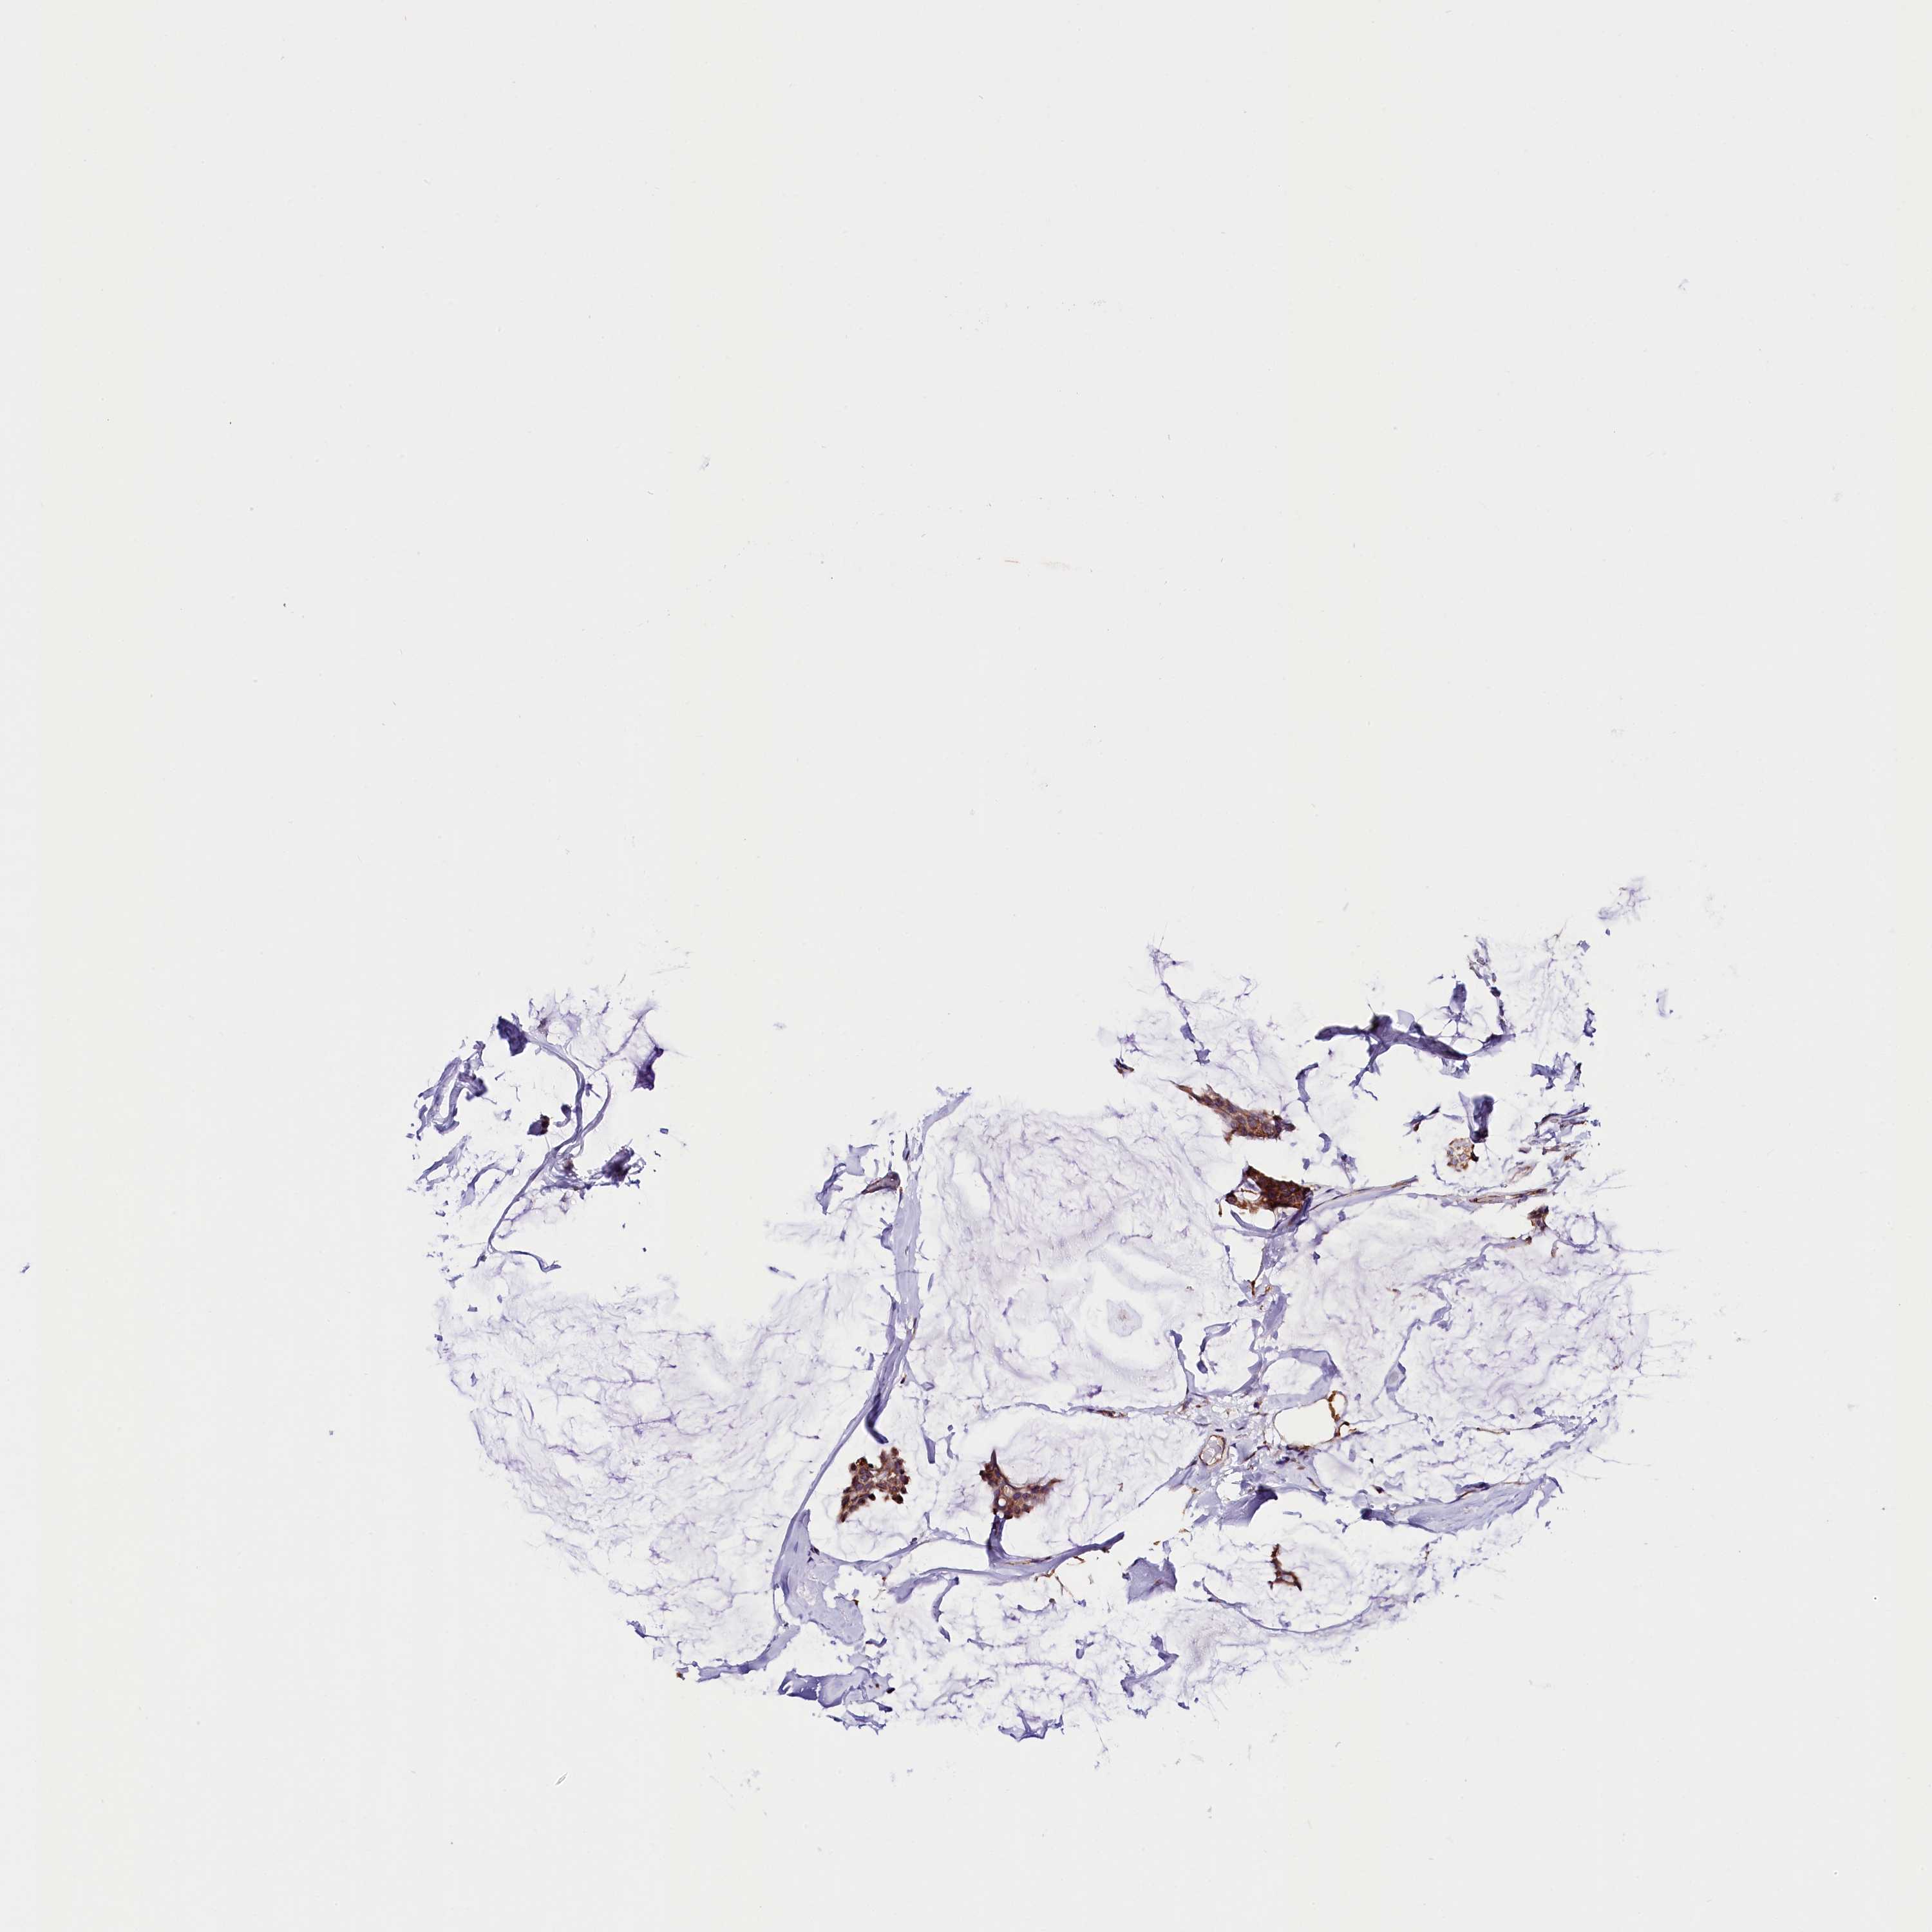

BRCA TCGA BRCA VALIDATION PROTEIN EXPRESSION

ANTIBODIES

AND

VALIDATION